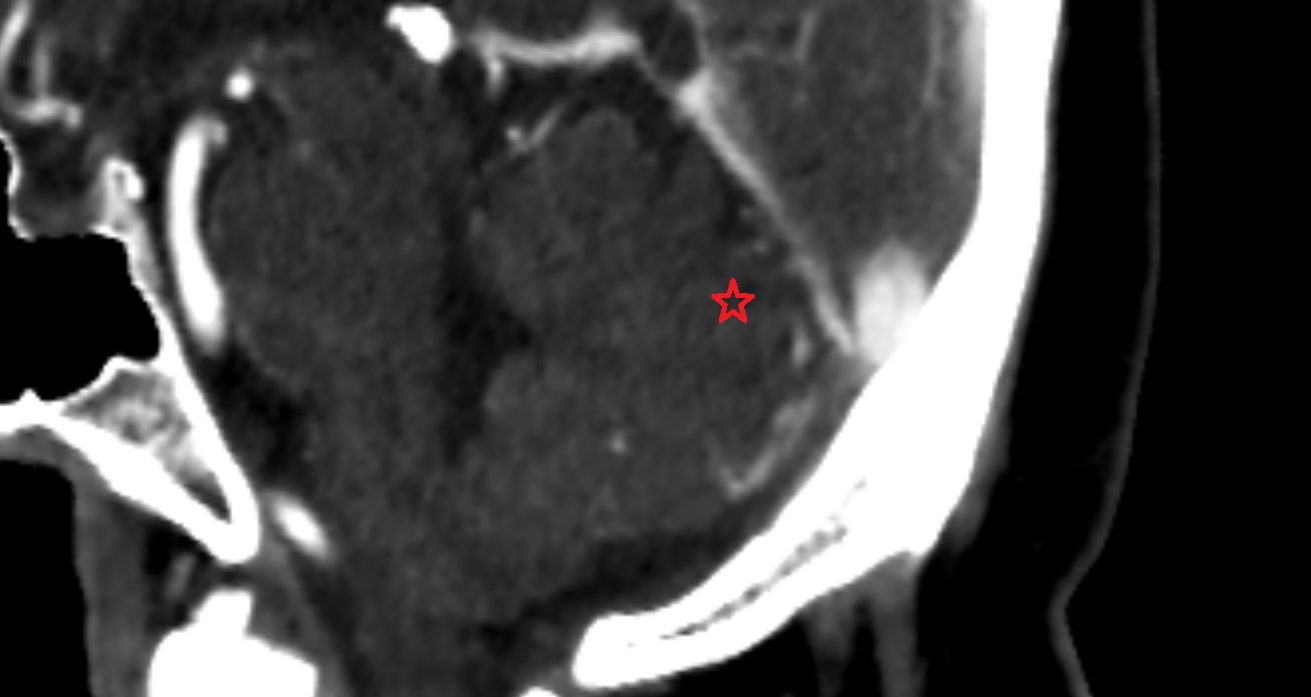

- Cerebellum

- Tonsil of cerebellum

- Cisterna magna